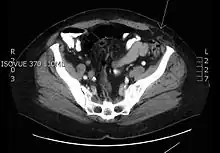

Transverse CT image of the abdomen in a patient with a Spigelian hernia (arrow).

Photograph by AfroBrazilian, distributed under a CC BY-SA 3.0 license.